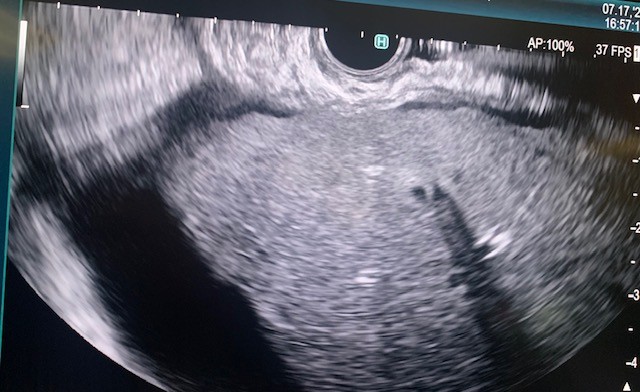

The side-viewing duodenoscope (Olympus) was passed to the duodenum and the major ampulla appeared normal in the second part of the duodenum. A Jagtome Rx 39 (Boston Scientific) with a loaded revolution Jagwire 0.025 was used to cannulate the common bile duct. Cholangiogram showed a very small bile duct, cystic duct and that the gallbladder was filled with a large amount of sludge. Sphincterotomy was performed over the guidewire, and a black pigmented stone was dislodged from the ampulla. Then the Jagwire was maneuvered into the gallbladder the cystic duct was dilated using a Hurricane balloon 4mm x 4cm (Boston Scientific) (Fig 3). A 7 french 15-cm double pig-tail plastic stent (Boston Scientific) was deployed, the proximal curled pigtail in the duodenum and the distal pigtail end was in the gallbladder through the ampulla (Fig 4). The contrast from the gallbladder was subsequently emptied out of the stent showing patency.

Figure 3. Fluoroscopic evaluation of balloon progression through the common bile duct and cystic duct.

Figure 3